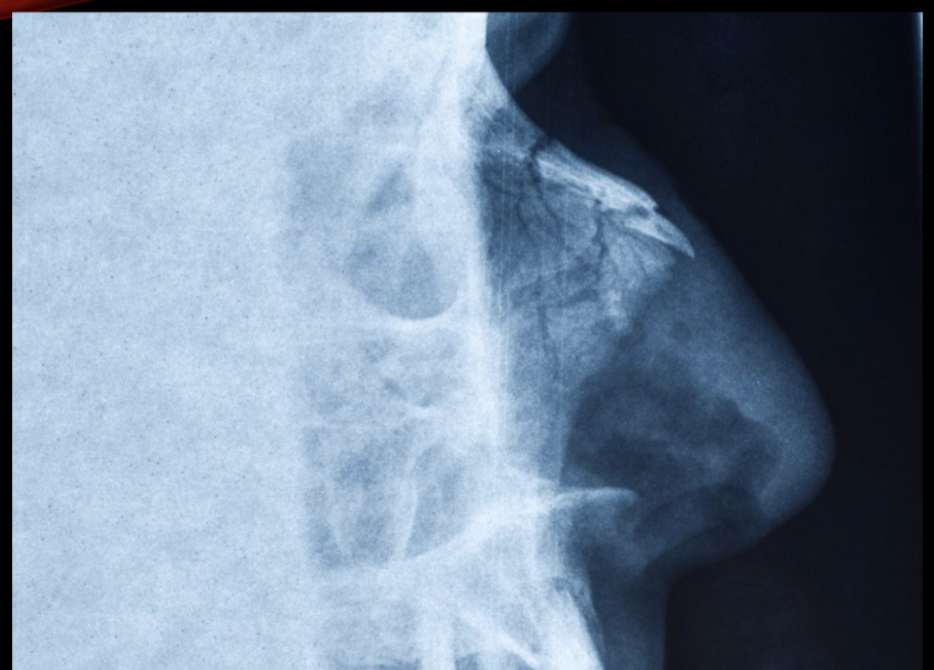

Nombre de la proyección y diagnóstico:

A

• Perfilograma

• Fractura de huesos propios conminuta